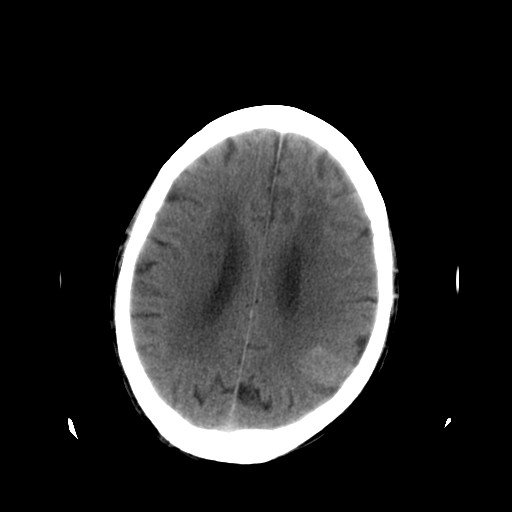

患者,男,70岁,清晨(10小时前)无法自行起床,家人无法唤醒,现昏迷,大小便失禁

左颞枕叶交界区可见类圆形高密度区,边缘可见环形更高密度影,并夹杂有点状钙化影,占位效应明显,未见明显水肿影,考虑脑膜瘤出血

肿快呈以等密度为主的等高密度影,占位效应不是很明显,只是左枕角受压,肿块内侧似有低密度改变.

单纯出血吸收应该从周边开始,

1脑膜瘤

2血管畸形

左颞枕叶交界区可见类圆形高密度区,边缘可见环形更高密度影,侧脑室后角明显受压而周围未见明显水肿.考虑脑膜瘤伴出血可能性大不排外血管畸形.建议mr进一步检查.

左侧颞枕叶交界区见类圆型等高密度混杂影,边缘可见高密度影环绕,同侧侧脑室后脚受压变形,周边围见明显水肿影. 结论:脑膜瘤首先考虑.